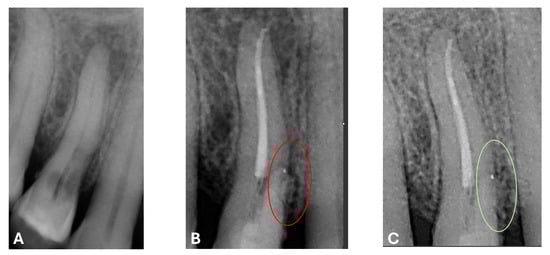

A CBCT examination (X9 Pro®, MyRay, Imola, Italy), performed with dedicated field of view (FOV) (6 × 6) and exposure parameters, was essential for accurate diagnosis and treatment planning. This device optionally features a specific Booster function for users with advanced expertise, which allows for further customization of exposure parameters to optimize the examination more effectively. Optimal management of the FOV, properly centered and limited to the anatomical area of interest, in this specific case slightly extended (6 × 6) to clearly rule out a possible involvement of the maxillary sinus in agreement with the attending otorhinolaryngologist, enabled the acquisition of broader and more detailed clinical and diagnostic information, which is essential in endodontics. Moreover, it allowed for a significant reduction in radiation dose while optimizing spatial resolution [22]. The imaging clarified the extent of the resorption and defined its perimeter, demonstrating an endodontic-periodontal communication, classified as 3Bp according to Patel’s classification [21] (Figure 2, Figure 3, Figure 4 and Figure 5).

Figure 3.

Cross-section and Pano-rex CBCT images of tooth 1.4 and its ECR and EPL. (A,B) Sequential sagittal scrolling allows the evaluation of the lesion in the bucco-lingual direction and its continuity along the root axis; (C,D) Segmentation of Figure 3B using the advanced software functions iRYS® (MyRay, Imola, Italy); (E) Interface of the aforementioned software to obtain segmentation on Pano-rex image. (F) Pano-rex image of tooth 1.4 and its EPL. (G,H) Segmentation of Figure 3F using the advanced software functions. The colored lines crossing the images represent the orthogonal planes (axial, coronal, and sagittal) in the multiplanar reconstruction. Their correct use and orientation allow for an accurate identification of the extent of the lesions in all spatial planes and a detailed analysis of the endodontic anatomy. The green letters are the coordinates of the image: A: anterior, B: bottom, T: Top.

Figure 4.

Pano-rex and cross-sectional CBCT images of tooth 1.4, showing its ECR, EPL, and PL. The colored lines crossing the images represent the orthogonal planes (axial, coronal, and sagittal) in the multiplanar reconstruction. Their correct use and orientation allow for an accurate identification of the extent of the lesions, including possible relationships with the maxillary sinus, in all spatial planes and a detailed analysis of the endodontic anatomy. The green and red letters are the coordinates of the image: A: anterior, R: right, B: bottom, T: Top.

An intermediate follow-up CBCT scan at 6 months was performed to accurately assess the response to treatment in light of both the extent of the lesion and the patient’s systemic comorbidities (Figure 10, Figure 11, Figure 12, Figure 13 and Figure 14).

Figure 10.

Axial CBCT images of tooth 1.4 after six months of healing. (A–F) Sequential scrolling of the root of tooth 1.4 after six months of healing.

Figure 11.

Cross-section CBCT images of tooth 1.4 after six months of healing. (A–I) Sequential scrolling of EPL healing.

Figure 12.

Pano-rex and cross-sectional CBCT images of tooth 1.4 after six months of healing. (A,B) Sequential scrolling of tooth 1.4 after six months of healing. The colored lines crossing the images represent the orthogonal planes (axial, coronal, and sagittal) in the multiplanar reconstruction. Their correct use and orientation allow for an accurate identification of the extent of the lesions in all spatial planes and a detailed analysis of the endodontic anatomy. The green and red letters are the coordinates of the image: A: anterior, R: right, B: bottom, T: Top.